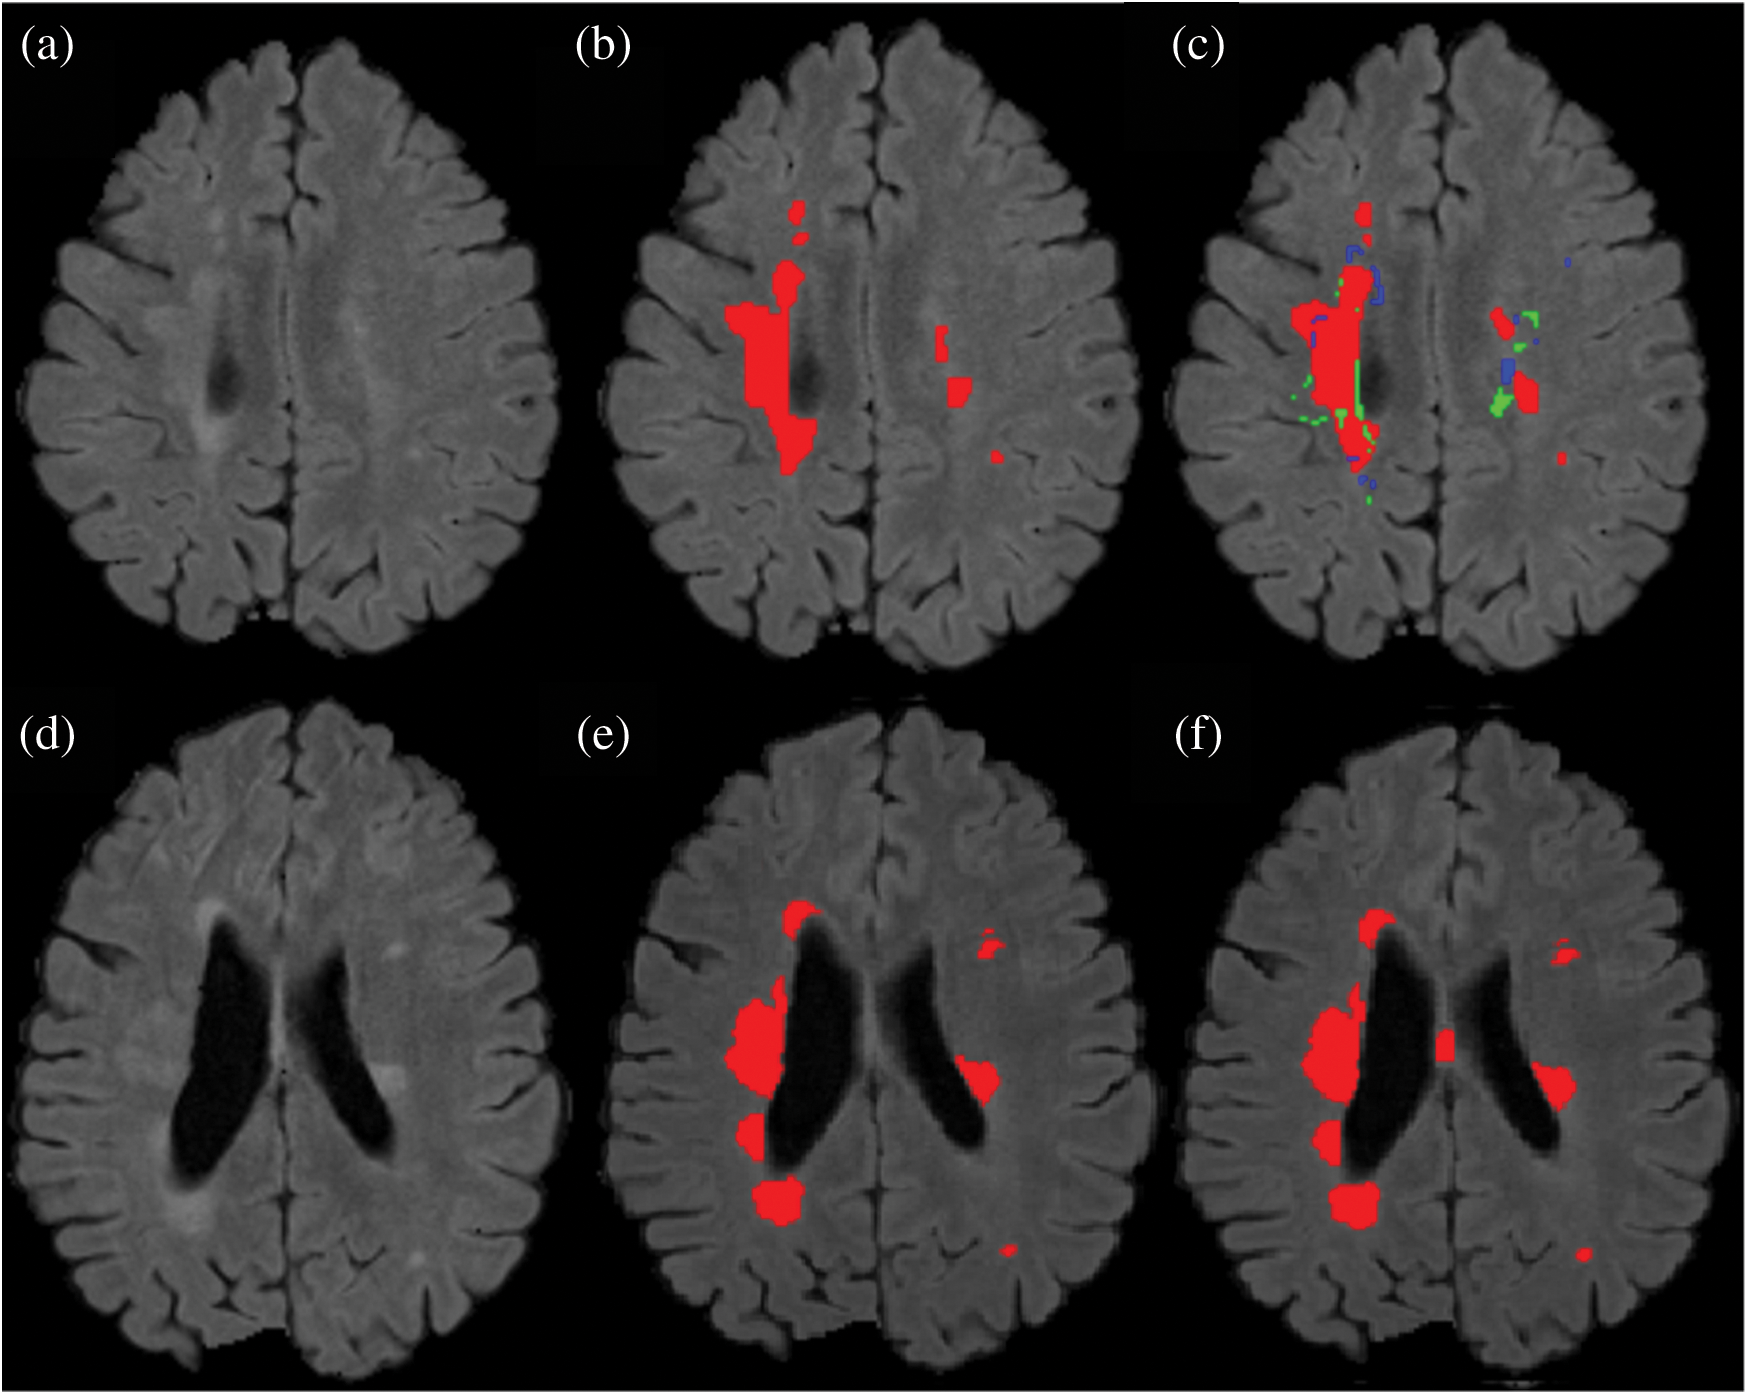

From the ISBI dataset, the results of the first 3 scans (ISBI 01, ISBI 02 and ISBI 03) are displayed in Tab. 3. ISBI results are evaluated on a qualitative and quantitative basis. Qualitative results can be seen in Fig. 3, whereas quantitative results have been shown in Tab. 3. Qualitative results in Fig. 3, show the original image, manually segmented image, proposed auto segmented image, and overlap of both manual and auto segmented images. Results show that our proposed method has good results for manual segmentation.

Figure 3: Qualitative results for ISBI dataset

In this section different state-of-the-art methods have been compared with the proposed method. All these methods used the same ISBI dataset and the same evaluation metrics as described in Section 3.3. Benchmark of the dataset was also provided on their website to compare the results. These benchmarks are manually annotated by the experts in the field of MS. These methods are evaluated by using various metrics like DSC, sensitivity, and precision. These results are tabulated as a mean of all results obtained with the help of the proposed method. The quantitative comparison of the proposed method with top rank existed methods is shown in Tab. 4. These values are extracted from the challenge website and some are extracted from their related publications. These results are considered best to date for the segmentation of lesions. The proposed method has more DSC as compared to all existed methods, where DSC is also called overall segmentation accuracy, described by ISBI challenge website. For the qualitative comparison with manually annotated lesions provided by ISBI are shown in Figs. 3, 4 and 7. To check the trade-off between sensitivity and precision, the receiver operating characteristic (ROC) curve is drawn for the proposed CNN approach on the ISBI dataset, shown in Fig. 6.

Figure 7: Comparison between the proposed method and manually segmented area/ground truth. (a) FLAIR image. (b) Manually segmented image. (c) auto segmented image / proposed method with true positive (red color), false positive (green color) and false negative (blue color). (d) FLAIR image of a second patient. (e) Manually segmented area of the second patient. (f) Auto/proposed segmented lesions of the second patient

Results show that the proposed method has excellent results not only in precision but also in speed and robustness as testing takes only 15 seconds on average for automatic segmentation of MS lesions. Some scans have less lesion load and some scans have more lesion load. Lesion load is referred as the volume or number of lesions. Average timing is calculated after calculating time for all available testing scans and then taking the average of all the values. In Fig. 7 the results are demonstrated qualitatively and can be compared with ground truth or manually segmented scans. The first row of Fig. 7 shows the results of the first tested scan and compared it with manually segmented masks. (a) shows the original FLAIR image and (b) displays a manual mask or ground truth. (c) is the automatic or proposed method that depicts different colors, where red is true positive, green is false positive, and blue is a false negative. Row 2 shows one more scan from the testing dataset. (d) is the original FLAIR image, (e) is manually segmented, and (f) is the automatic proposed method. After a qualitative comparison, it is clear that the proposed method segments lesions automatically and very accurately.